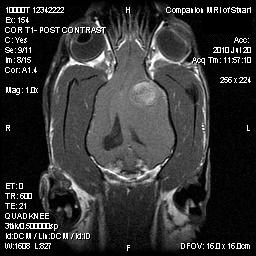

Companion MRI is the only full-time small-animal veterinary magnetic resonance imaging center in central Connecticut serving clients from all over New England, New York, and New Jersey. MRI for dogs and cats has the same clinical indications and diagnostic benefits as MRI scans for humans. We are excited to offer this affordable, superior diagnostic tool to all veterinarians and clients.